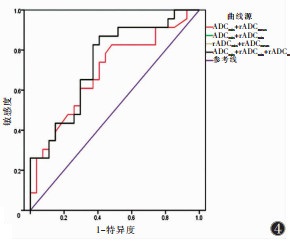

采用logistic回归分析及ROC曲线分析ADCmin、rADCmin、rADCmean联合对直肠癌淋巴结转移的预测效能,AUC为0.692~0.738(图 4),敏感度为82.6%~87.0%,特异度为51.9%~59.3%。

| 注:其中ADCmin+rADCmin、rADCmin+rADCmean、ADCmin+rADCmin+rADCmean预测区域转移淋巴结的ROC曲线(黑色)重叠。 图 4 ADCmin、rADCmin、rADCmean两两联合及三者联合预测区域转移淋巴结的ROC曲线 |